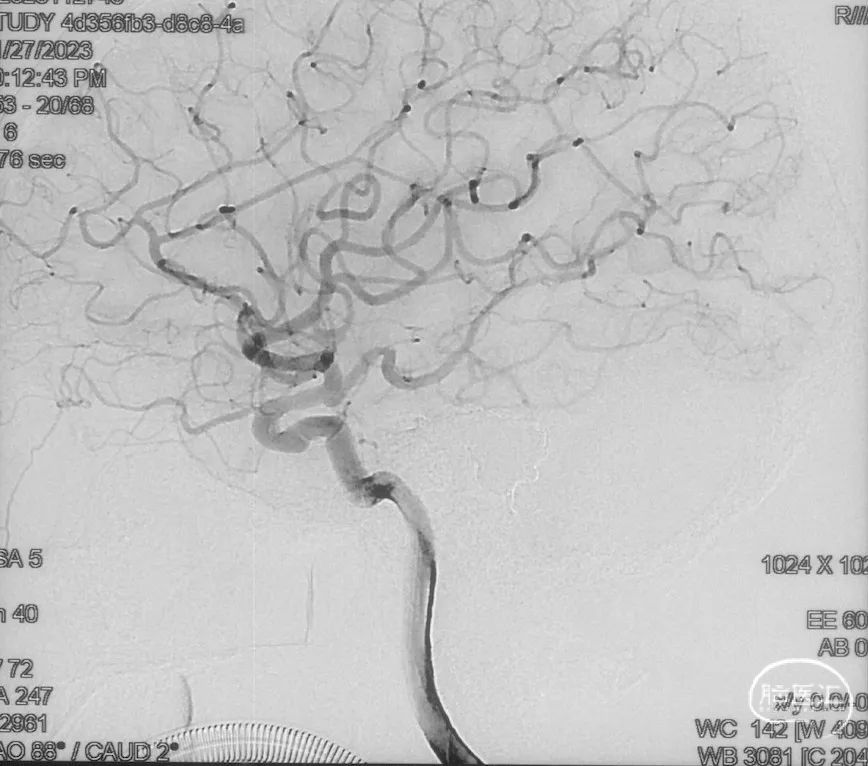

术前造影

证实为TDAVF,为岩上窦型。R-ECA正侧位见右侧脑膜中动脉分支、枕动脉分支、颞浅动脉分支向瘘口供血,经幕上迂曲扩张的静脉、中脑周围静脉、基底静脉向深部静脉引流。

R-ICA正侧位见右侧脑膜垂体干向瘘口供血

L-ICA正侧位见左侧脑膜垂体干分支向瘘口供血

L-ECA正侧位未见向瘘口供血

L-VA、R-VA正侧位右侧小脑上动脉脑膜支向瘘口供血

选取工作角度,正侧位造影